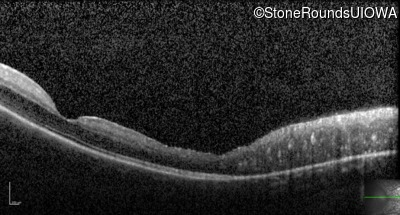

Optical Coherence Tomography - Left - 20/32

Exemplar / OCT Stack